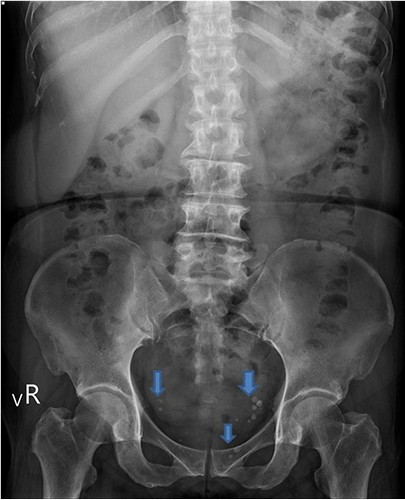

圖:骨盆底肌肉筋膜炎的臨床表現,是內診時會觸碰到「結節性痛點」(MTrPs,藍箭頭處),約0.5公分「凸起結節」,且一碰就痛。

女性「骨盆底肌肉筋膜炎」(Myofascial pelvic pain, 簡稱MFPP) ,最主要的症狀表現就是慢性反覆性下腹痛,龐渂醛醫師表示,女性的慢性下腹痛原因很多,包括常見的骨盆腔發炎、膀胱發炎、便秘、間質性膀胱炎和內膜異位症等,其中預估超過一半的比例合併有骨盆底肌肉筋膜炎。因此,需先檢查或排除其他下腹痛的原因,才能診斷骨盆底肌肉筋膜炎。單純性骨盆底肌肉筋膜炎的臨床表現是內診檢查骨盆底肌肉筋膜時,會觸碰到「結節性痛點」(Myofascial trigger points,MTrPs)。正常情況下的肌肉筋膜為軟質平滑,一旦有「結節性痛點」,會有0.5公分「凸起結節」,且一碰就痛,即為骨盆底肌肉筋膜炎。